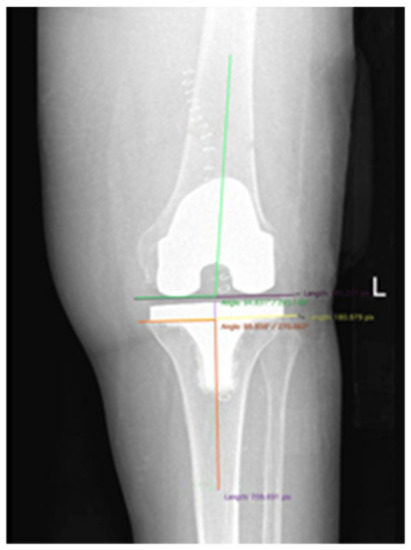

| Radiological Parameters | Varus (+) Valgus (−) PRE | Varus (+) Valgus (−) POST | Femoral Coronal Alignment | Tibial Coronal Alignment | |

|---|---|---|---|---|---|

| CONV | Mean | 4.15 | 0.41 | 93.98 | 89.77 |

| N | 61 | 61 | 61 | 61 | |

| Std. Deviation | 4.52 | 2.22 | 2.01 | 1.09 | |

| Minimum | −7 | −4 | 87 | 88 | |

| Maximum | 10 | 5 | 98 | 93 | |

| NAVI | Mean | 4.28 | 0.44 | 94.11 | 89.97 |

| N | 42 | 42 | 42 | 42 | |

| Std. Deviation | 6.18 | 2.40 | 2.06 | 0.65 | |

| Minimum | −10 | −4 | 89 | 89 | |

| Maximum | 15 | 5 | 98 | 91 | |

| Total | Mean | 4.26 | 0.43 | 94.04 | 89.86 |

| N | 103 | 103 | 103 | 103 | |

| Std. Deviation | 5.29 | 2.29 | 2.02 | 0.92 | |

| Minimum | −10 | −4 | 87 | 88 | |

| Maximum | 15 | 5 | 98 | 93 |